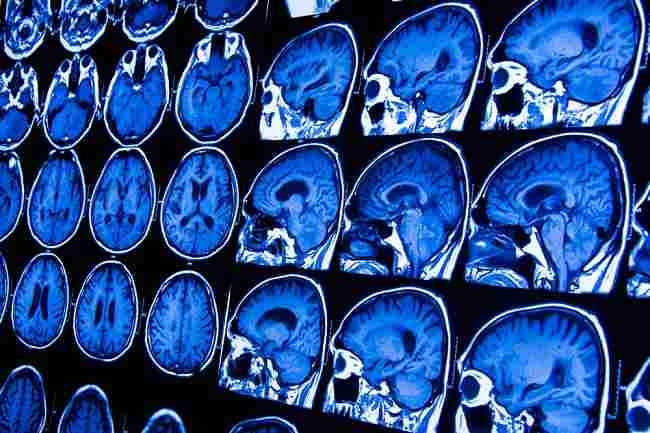

Batang otak adalah bagian otak yang terletak di dasar otak dan terhubung ke saraf tulang belakang. Selain itu, bagian otak ini juga berperan sebagai penghubung antara otak besar (cerebrum), otak kecil (cerebellum), dan saraf tulang belakang.

Anatomi Batang Otak

Otak dan batang otak di dalam kepala dilindungi oleh beberapa lapisan pelindung. Bagian terluar dilindungi oleh rambut dan kulit kepala, kemudian di bawahnya terdapat tulang tengkorak.

Sementara di bawah tulang tengkorak terdapat meningen atau selaput otak dan sumsum tulang belakang. Di antara selaput otak dan jaringan otak, terdapat cairan otak yang disebut juga cairan serebrospinal.

Batang otak terdiri dari beberapa bagian, yakni: